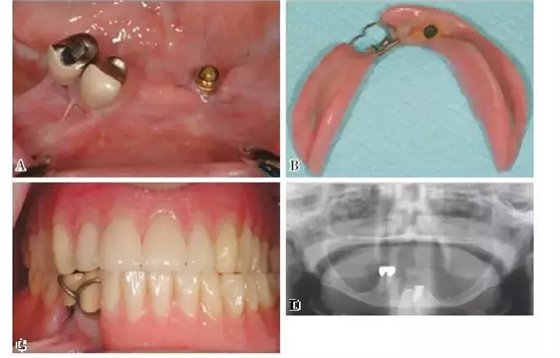

圖3:下頜KennedyⅠ類缺損。 剩余牙槽嵴顯著吸收伴有22號(hào)牙的缺失。種植體的使用提供了足夠的固位力,改善了義齒的舒適性和咬合功能